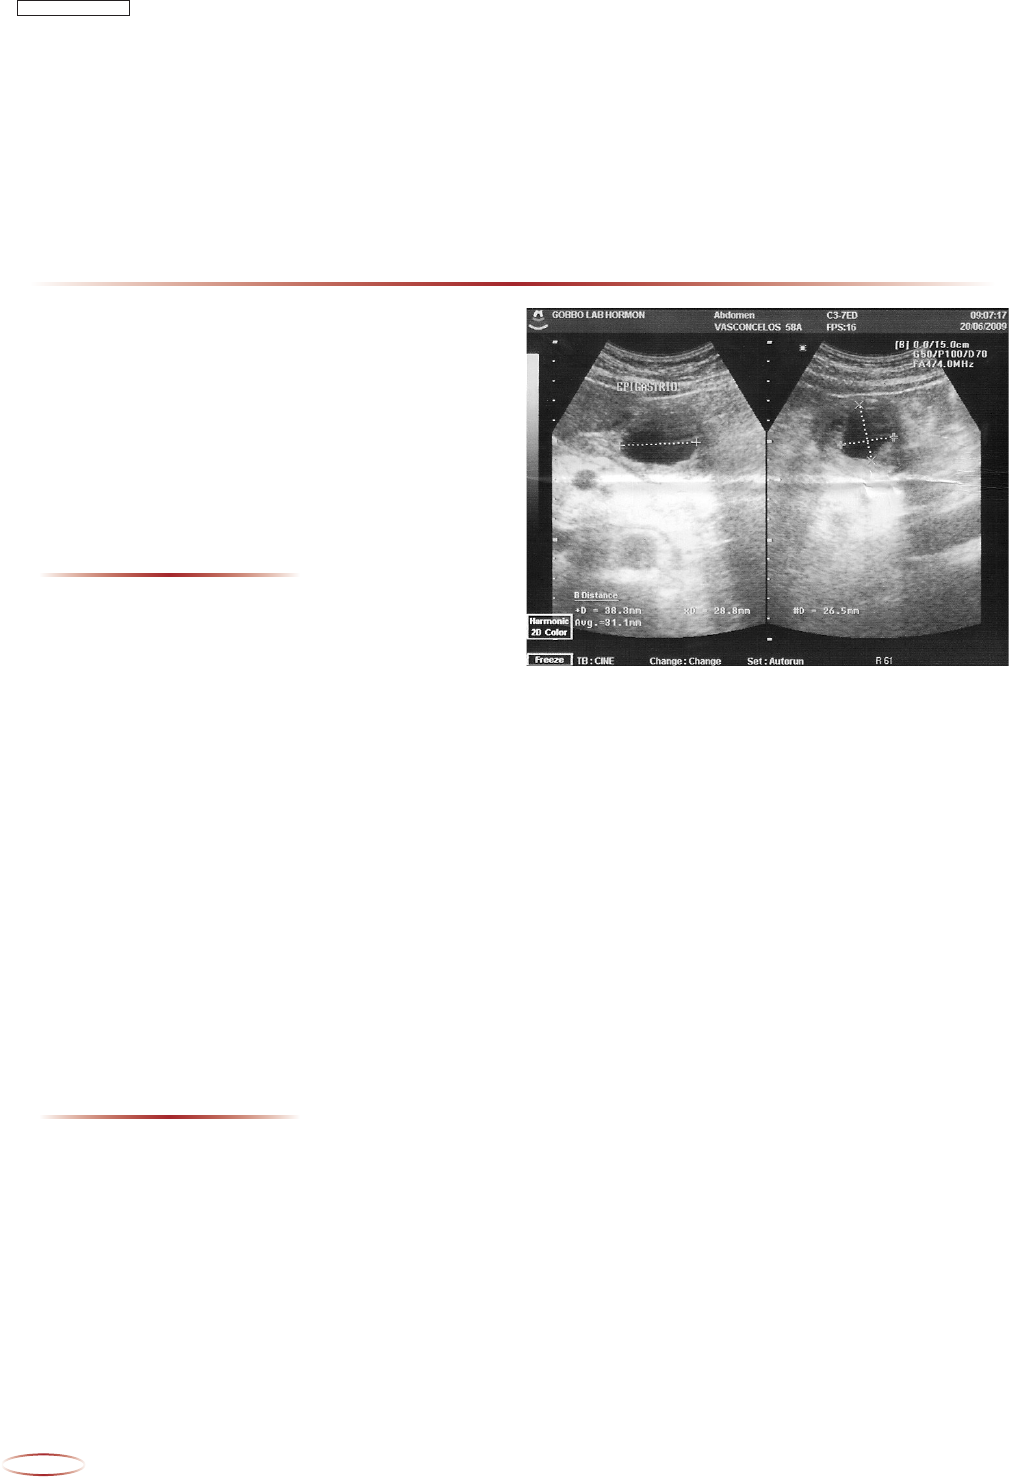

Ultrassom abdominal mostrou cálculos biliares e uma

formação cística, expansiva, sólida em epigástrio de

causa desconhecida (Figura1).

FIGURA 1 - Lesão epigástrica sólido-cística com significativa

área central cística